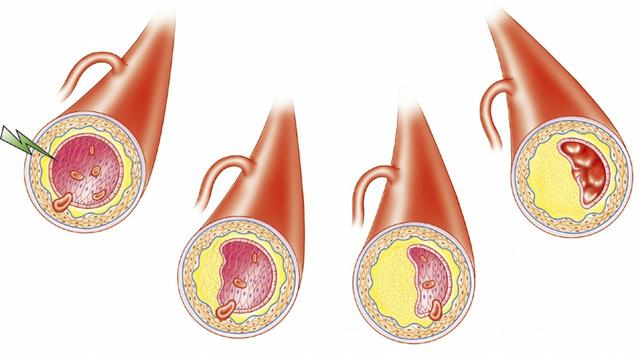

冠動脈疾患の最も直接的な原因は、プラークの形成によるものである。

私たちが通常プラークと呼んでいるものは、アテローム性動脈硬化症としても知られている。基本的に、体中のすべての動脈にプラークができる可能性があるが、心臓の冠動脈、頸動脈、脳の動脈はプラークができやすい。

同じ意味で、冠動脈疾患は冠動脈にプラークが増える病気である。プラークが血管を塞ぎ、血管の遠位端で慢性虚血が起こる。

- プラークが大きくない場合は、心臓にあまり影響を与えないかもしれない。プラークが血管の半分、つまり50パーセントをふさいでいれば、冠動脈性心疾患とみなされる。

- 急性心筋梗塞:プラークが突然破れると血栓が形成され、血管が完全に閉塞し、血管の遠位部まで血液が完全に行き渡らなくなる。この場合、急性心筋梗塞が起こる。

簡単に動脈硬化の形成と発展過程を紹介する:私たちの血管はもともと滑らかで弾力性があり、血液の重要な組織器官を輸送しているが、加齢や高血圧、糖尿病などの疾病因子の増加により、血管壁の内皮細胞は徐々に炎症反応が発生し、炎症反応のために血管壁の内壁が損傷し、一方では血管壁の損傷した内壁に損傷があり、それは血液を遮断する。一方では、血管壁の損傷した裏地は、血液の流れをブロックし、その結果、血液の流れが影響を受け、他方では、より多くの脂質廃棄物が徐々に損傷した部分の下に沈着物を形成するでしょう。

脂質は血管壁の内膜の下に沈着し、身体はそれを貪食するためにマクロファージを送り込んでストレスを与え、貪食の間にマクロファージは脂質をさらに酸化させて気泡を形成し、この気泡が融合して集まり、脂質コアが形成される。 血管壁の内膜の損傷を修復するために、私たちの血管は脂質コアの上にも被覆繊維性キャップを形成し、このような脂質コアを含み繊維性キャップで覆われた「プラーク」が形成される。脂質のコアの内膜への損傷を修復するために、私たちの血管はまた、脂質のコア、そのような脂質のコア、"プラーク "の被覆繊維性キャップの上に被覆繊維性キャップを形成することになる、そのようなプラーク、および外側に成長するのではなく、内側にパイプラインスペースの血管を混雑し、動脈平滑筋はまた、炎症反応の影響に起因することになる3つの高と遅い病気の影響は徐々に変性、弾力性が徐々に弱まり、そのようなプロセスは、動脈硬化、狭窄の形成である。これは、動脈硬化と狭窄形成の基本的なプロセスです。